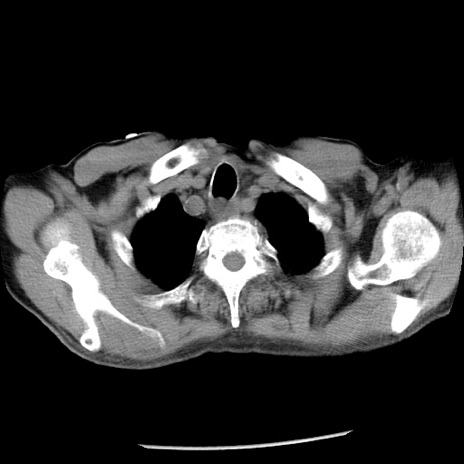

症例26(横断像)

【症例】80歳代男性

【主訴】嘔吐

【現病歴】昨晩2回嘔吐あり、今朝になっても嘔吐あり。来院。

【既往歴】胃潰瘍

【身体所見】意識清明、BT 37.6℃、BP 166/95mmHg、HR 100bpm、SpO2 97%、腹部:平坦・軟、腸蠕動音聴取良好、圧痛なし。

【データ】WBC 21900、CRP 1.46